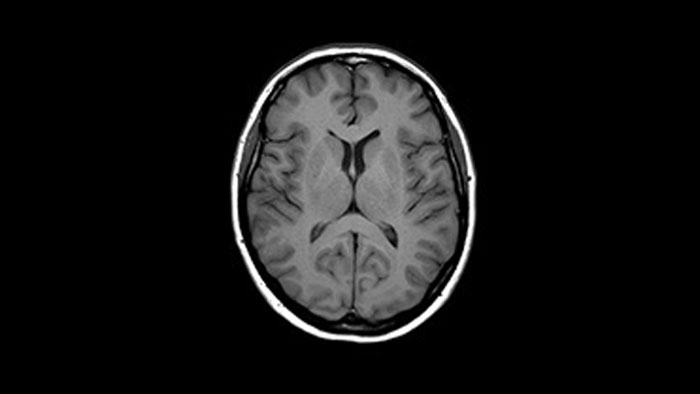

Brain image

Brain with glioblastoma